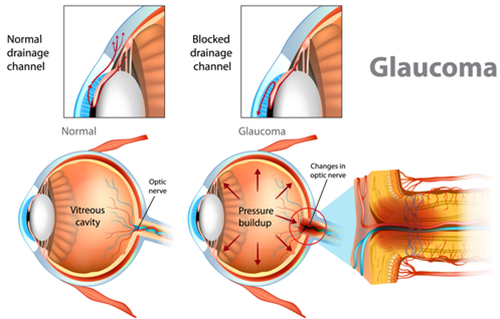

小梁切除术:针对开角型青光眼,通过改良缝合技术减少术后低眼压风险,单眼手术时长缩短至25分钟。

青光眼引流阀植入术:采用3D导航系统定位,植入比较准度提升,尤其适合难治性青光眼患者。

复合式小梁切除:结合抗代谢药物应用,手术可行性提升,尤其适合年轻患者。

激光虹膜边缘成形术:针对急性青光眼发作,10分钟内快速降低眼压,避免视力进一步损伤。

青光眼白内障联合手术:一次手术解决两种眼病,减少患者反复麻醉风险,术后视力修复周期缩短。

小创口青光眼手术(MIGS):通过微小切口植入iStent引流管,创伤小,适合早期青光眼患者。

前房穿刺术:针对急性青光眼眼压飙升,30秒内完成房水释放,快速缓解眼痛症状。

选择性激光小梁成形术(SLT):没有创口治疗早期青光眼,可重复操作,避免药物副作用。

个性化小梁切除术:根据角膜生物力学数据调整手术参数,术后散光发生率降低。

青光眼引流阀动态调节术:通过智能阀门控制房水流出量,避免术后眼压波动。